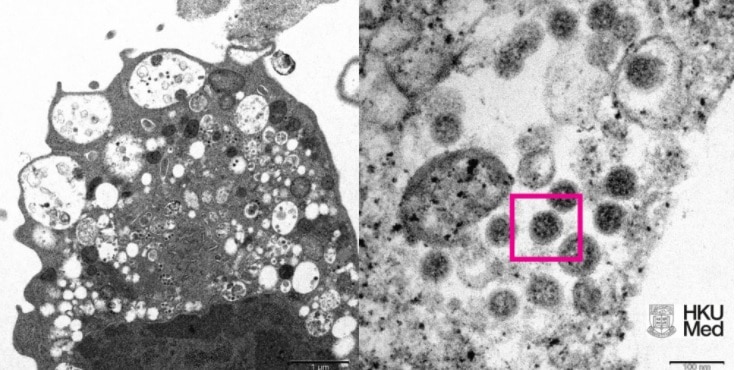

A variante Ômicron do coronavírus, que é mais infecciosa, parece provocar formas menos graves da doença do que a Delta, mas não deve ser classificada como “leve”, avisa a Organização Mundial da Saúde (OMS).

O Ômicron é um vírus que mata menos, mas em contrapartida se espalha muito mais rápido. Portanto, todo cuidado é pouco. Use máscara, higienize as mãos com álcool em gel 70º e evite aglomerações.